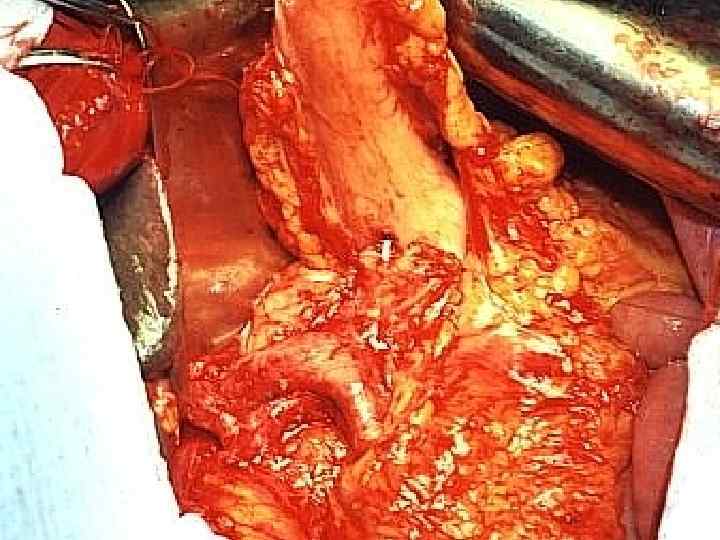

Этапы стандартной ГПДР • • • 1. Мобилизация 12 -перстной кишки 2. Выделение трубчатых структур гепато-дуоденальной связки 3. Выделение верхней брыжеечной вены 4. Мобилизация и отсечение дистальной части холедоха 5. Мобилизация и пересечение начальной части тощей кишки 6. Пересечение гепатикохоледоха после мобилизации желчного пузыря • 7. Пересечение поджелудочной железы по перешейку • 8. Пересечение связок крючковидного отростка, удаление комплекса • 9. Реконструктивный этап

Инвазия чревного ствола и общей печеночной артерии